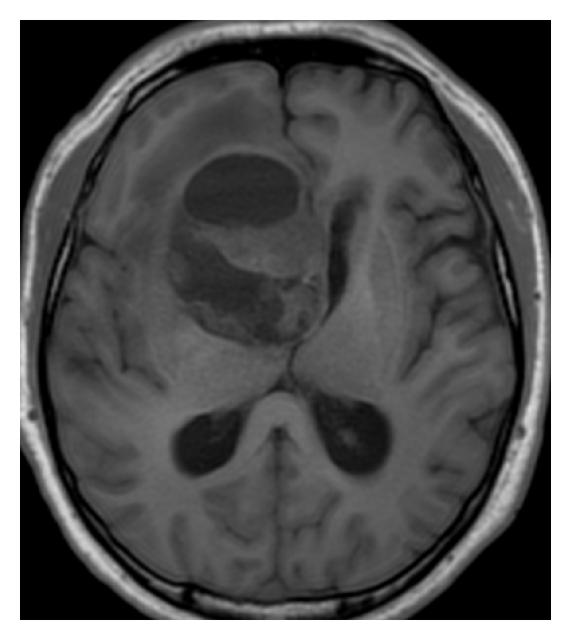

A 42-year-old Japanese man was admitted to our hospital for headache and nausea. These symptoms had progressed for 4 days before admission, and he was gradually unable to walk steadily. Magnetic resonance imaging (MRI) revealed a mass lesion with marked cyst components. The lesion had a maximum diameter of 58 mm (Figure 1). T1-weighted images (WIs) after gadolinium administration showed ring enhancement. T2WIs showed slight edema around the lesion. Proton magnetic resonance spectroscopy (1H-MRS) analysis of the nodule showed an increased ratio of choline to creatine and an apparent peak for lactate, which is strongly correlated with tumor malignancy. In contrast, the peak for N-acetylaspartate (NAA) was within the background noise level (Figure 2). The neuroimaging diagnosis was a primary malignant brain tumor such as glioblastoma multiforme (GBM) or a metastatic brain tumor. The patient underwent subtotal removal of the lesion via a fronto-temporal craniotomy.

(a)

(b)

(c)

(d)